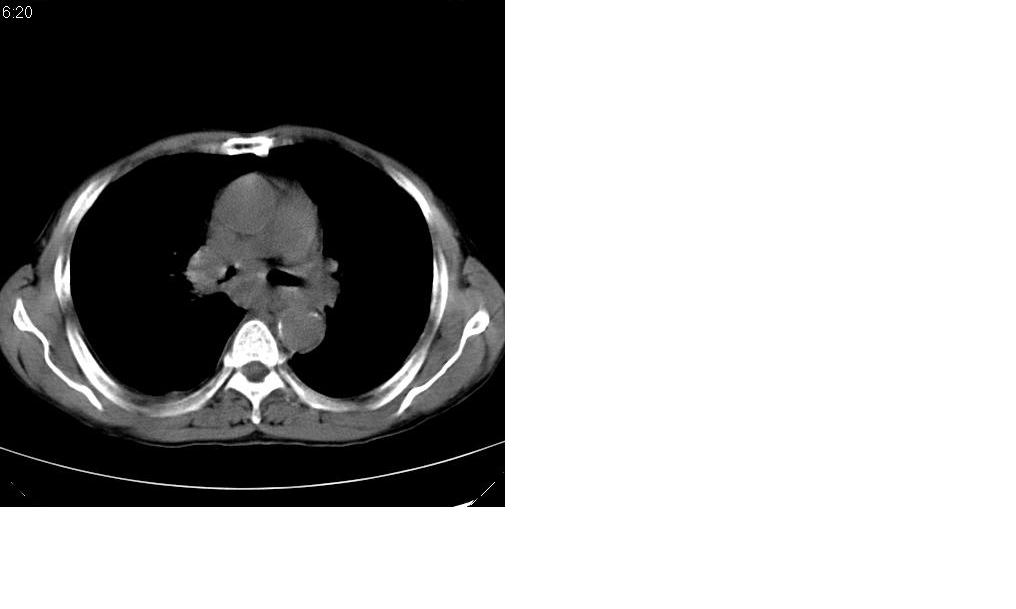

标题: CT10843:男 61岁,胸部CT平扫 [打印本页]

标题: CT10843:男 61岁,胸部CT平扫

男 61岁,已确诊肺癌半年余.

右肺小细胞肺癌并纵隔淋巴结转移。胸腔积液,心包少量积液。左肺改变不除外癌性淋巴管炎

考虑:1、右肺下叶中心型肺癌并纵隔淋巴结转移。胸腔积液。

2、心包少量积液。

3、左肺改变不除外癌性淋巴管炎或化疗后肺间质纤维化。